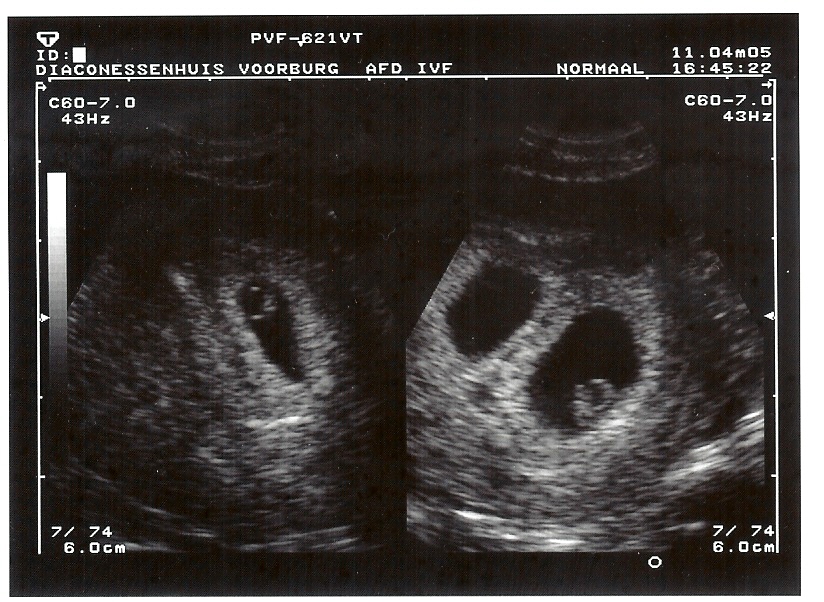

11-4-2005 Beide 6 weken en 4 dagen

11-4-2005 Charmain 6 weken, 4 dagen, 4.9mm

11-4-2005 Danique 6 weken, 4 dagen, 5.5mm